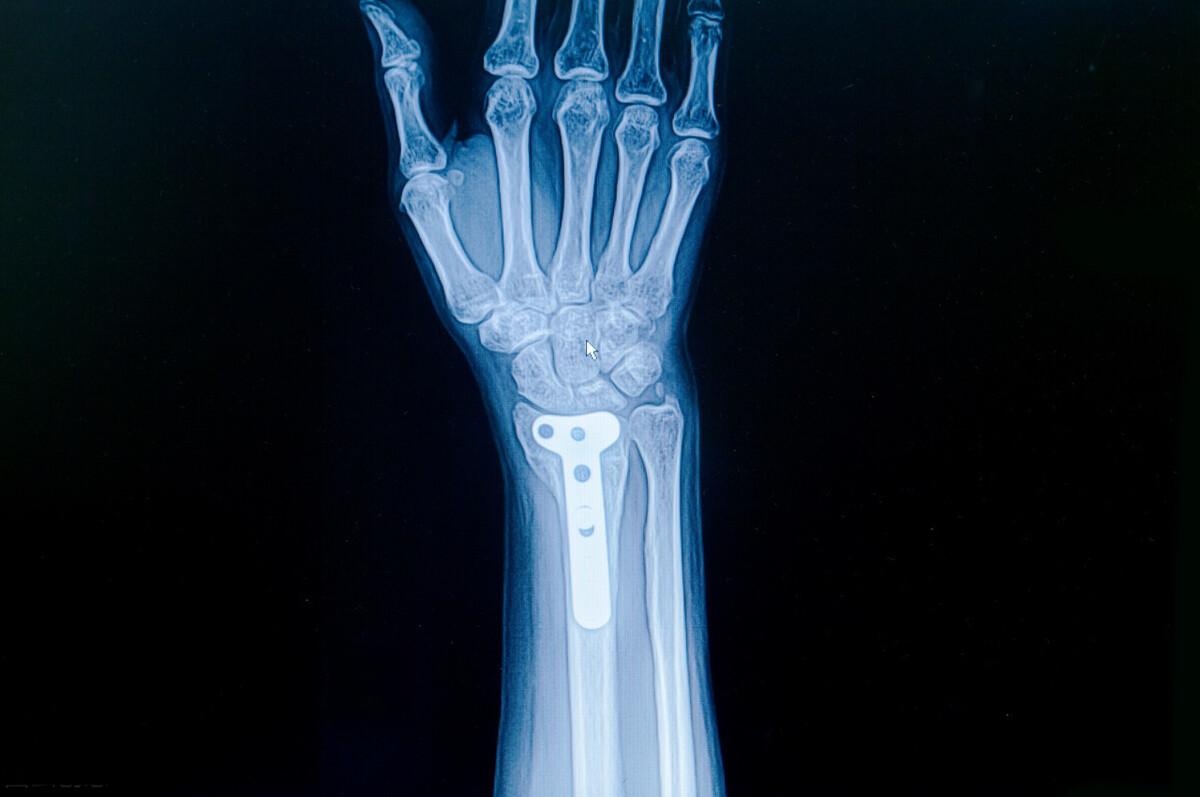

作为一名康复治疗师,我经常遇到腕部桡骨远端骨折的患者。这种骨折通常发生在跌倒时用手撑地的情况下,常见于老年女性。治疗方式包括保守治疗(如夹板或石膏固定)和手术治疗。无论采用哪种治疗方式, 正确的康复训练对于恢复手腕功能都至关重要。

大约6周后,如果X光检查显示骨折愈合良好,就可以拆除夹板了。 这个阶段的康复重点是恢复腕关节和前臂的活动度,让受伤的手臂重新参与日常活动。

4. 定期复查:定期进行X光检查,确保骨折愈合良好,及时调整康复计划。